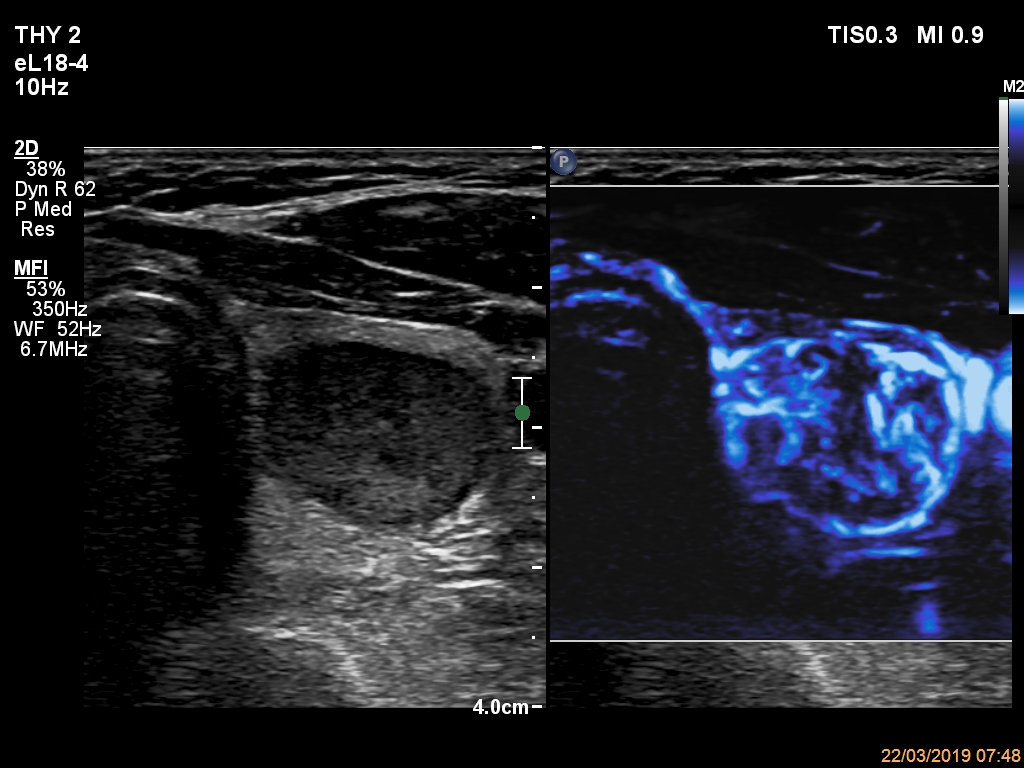

Ultrasonography. The thyroid was echonormal and had multiple nodules. The only lesion of a possible oncological importance was in the left lobe. It was hypoechoic. The dimensions were 16x14x23 mm (width, depth, length, respectively). The lower border presented an undulation which was caused by another, hyperechoic nodule. The nodule presented a predominant perinodular blood flow and had an average rigidity on elastography.